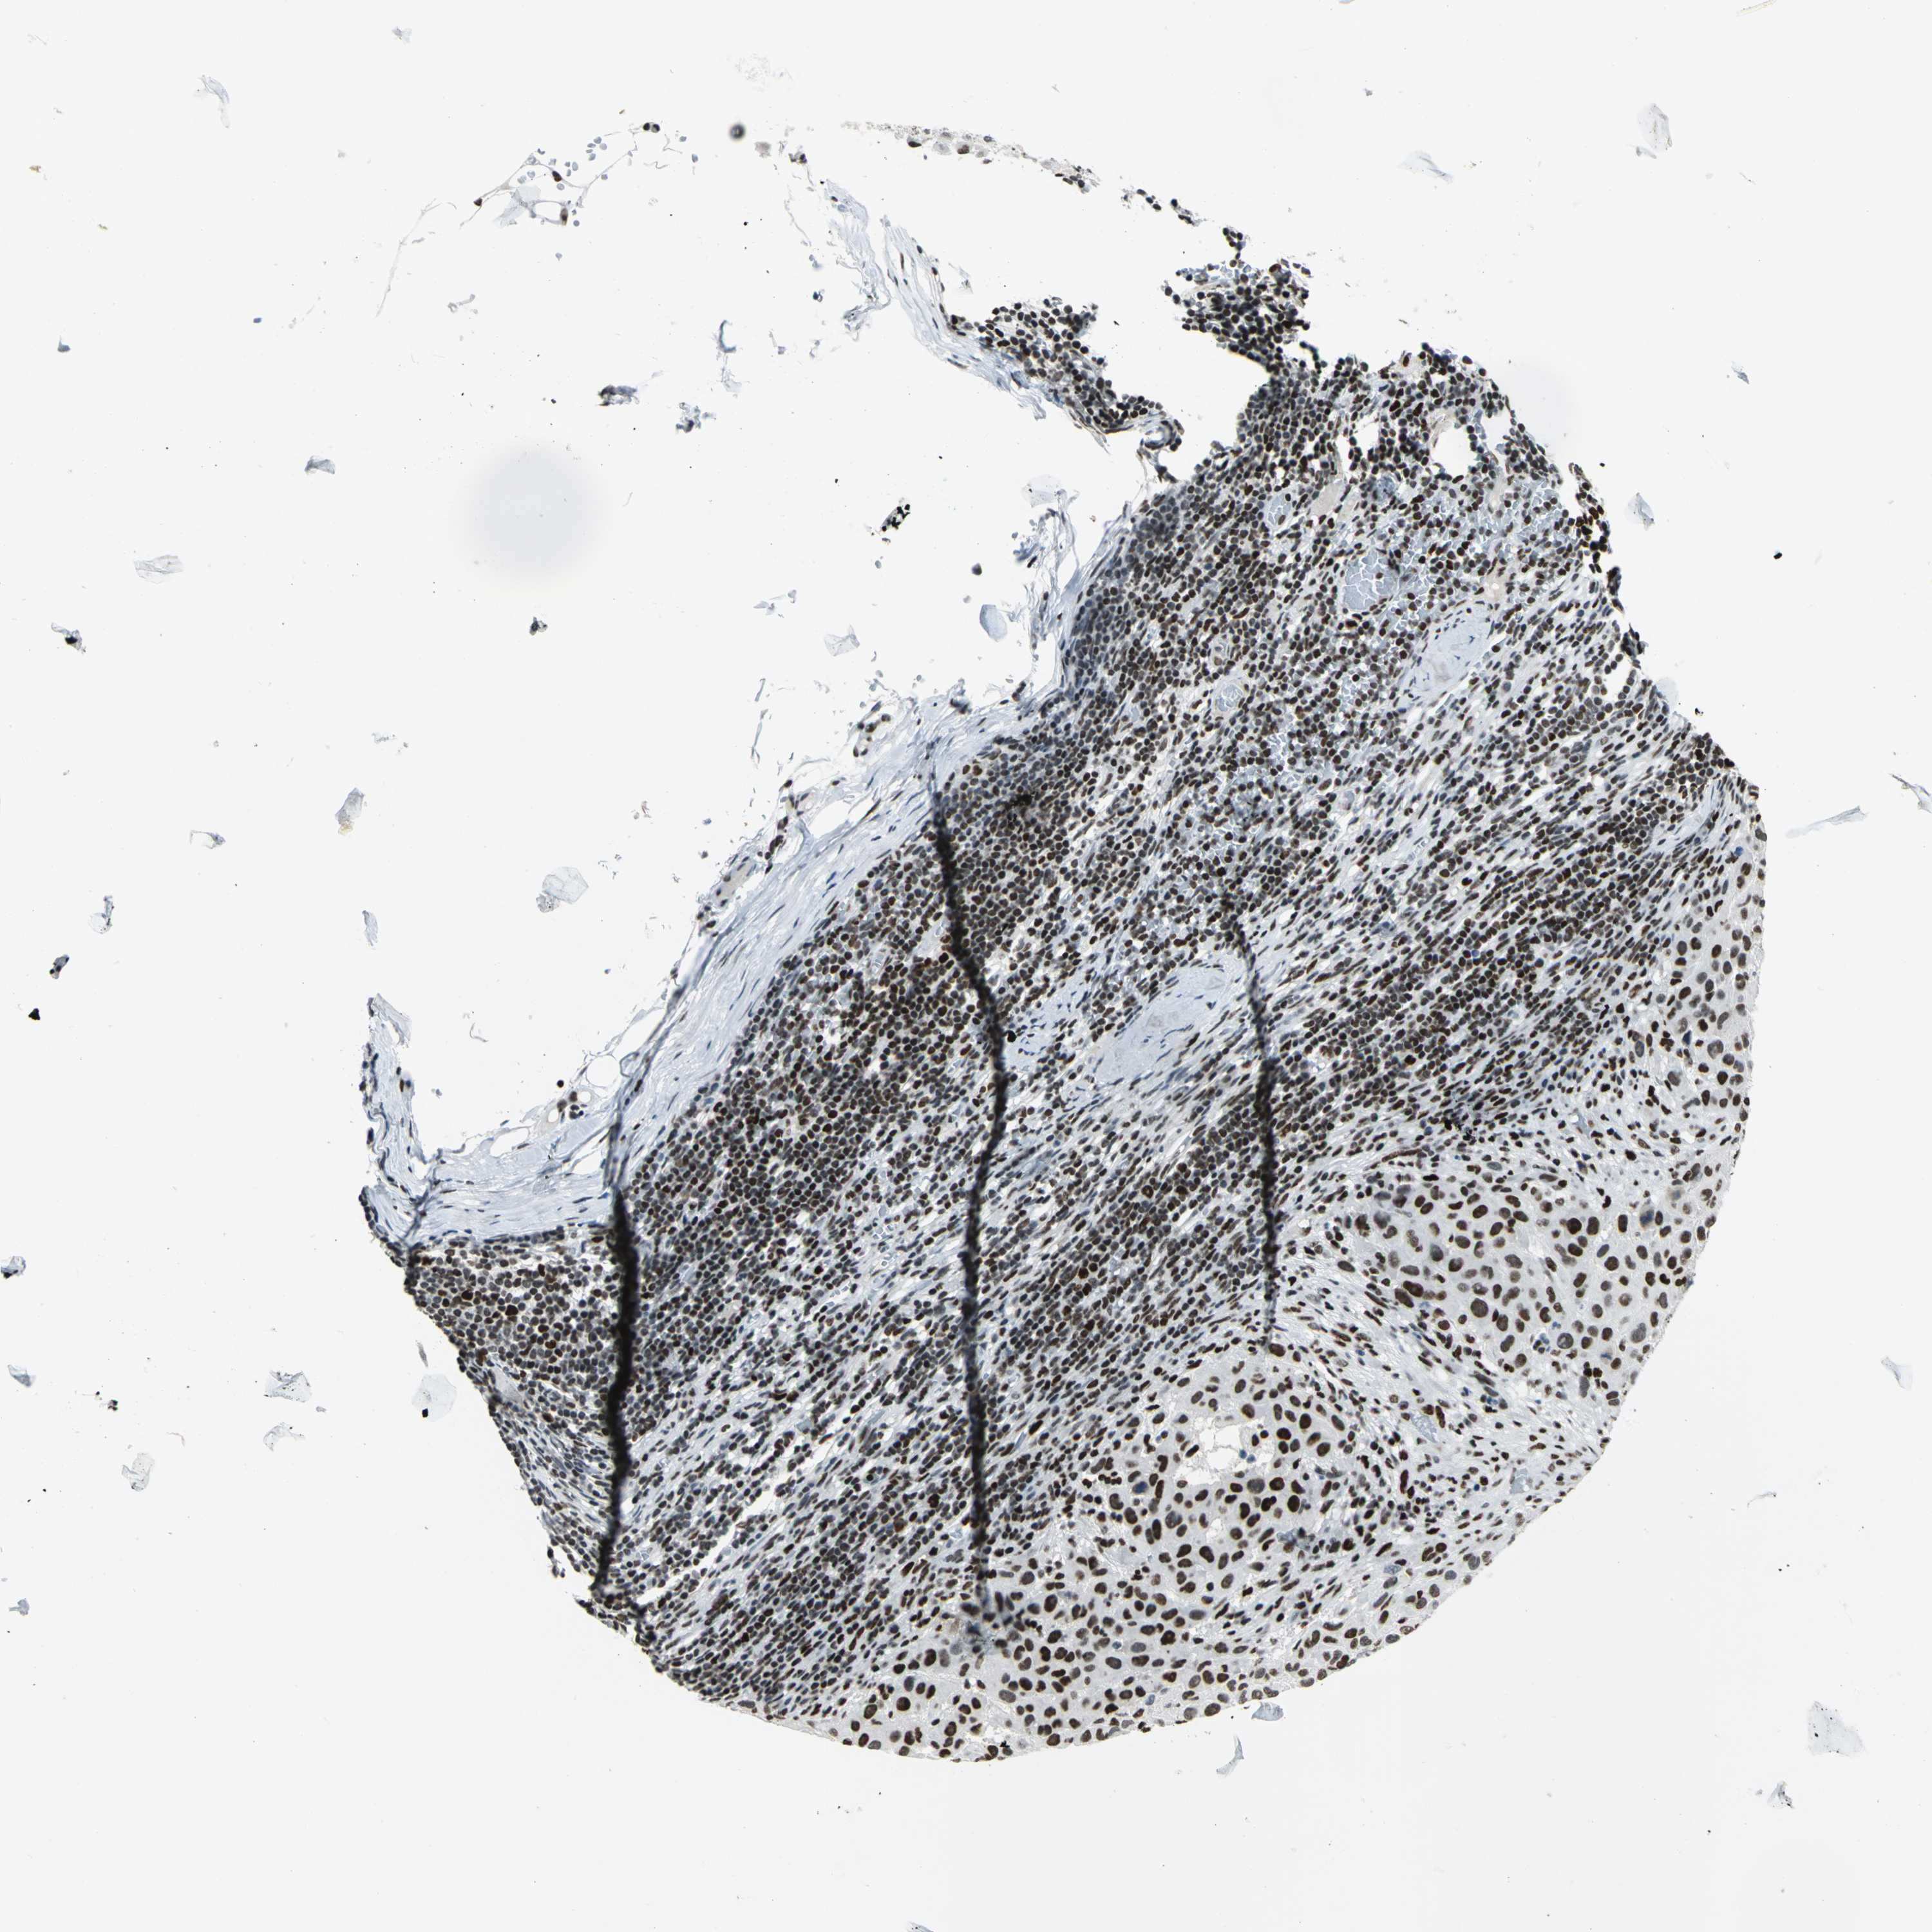

MELANOMA - Protein expressioni

A mouse-over function shows sample information and annotation data. Click on an image to view it in a full screen mode. Samples can be filtered based on level of antibody staining by selecting one or several of the following categories: high, medium, low and not detected. The assay and annotation is described here.

Note that samples used for immunohistochemistry by the Human Protein Atlas do not correspond to samples in the TCGA dataset.

Antibody stainingi

Antibody staining in the annotated cell types in the current human tissue is reported as not detected, low, medium, or high, based on conventional immunohistochemistry profiling in selected tissues. This score is based on the combination of the staining intensity and fraction of stained cells.

Each image is clickable and will lead to virtual microscopy that enables deeper exploration of all samples and also displays staining intensity scores, fraction scores and subcellular localization as well as patient and tissue information for each sample.

Antibody HPA004911

Staining

High

Medium

Low

Not detected

Intensity

Strong

Moderate

Weak

Negative

Quantity

>75%

75%-25%

<25%

None

Location

Nuclear

Cytoplasmic/membranous

Cytoplasmic/membranous,nuclear

Malignant melanoma, NOS

Malignant melanoma, Metastatic site